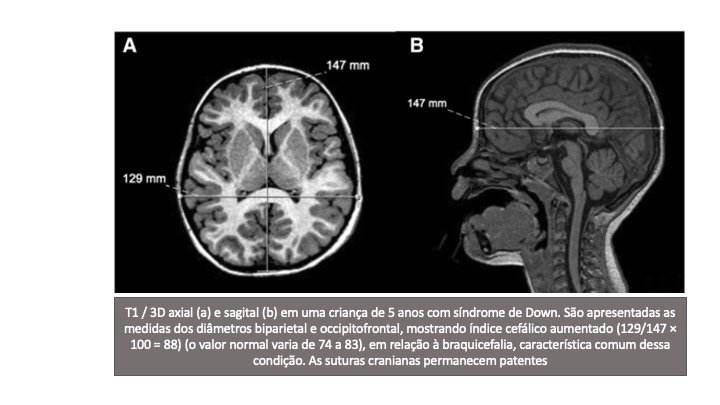

Estes incluem mais frequentemente a redução no tamanho da cabeça (microcefalia) associada a um alargamento anormal do diâmetro transversal, um achado conhecido como braquicefalia. Portanto, na braquicefalia, a relação entre o diâmetro biparietal (DBP) e o diâmetro occipitofrontal (OFD) (correspondente ao índice cefálico) aumenta e se aproxima do percentil 95.

Esta característica pode ser identificada visualmente e pode ser avaliada em estudos de neuroimagem (FIGURA 1).

Embora a braquicefalia seja frequentemente causada por craniossinostose envolvendo as suturas coronal e lambdoide, limitando o crescimento ântero-posterior do crânio, na SD, as suturas geralmente permanecem patentes.